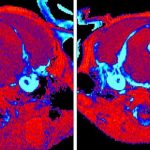

Immagine confocale che rappresenta l'immunomarcatura di AgRP e sinaptofisina TdTomato

Immagine confocale che rappresenta l’immunomarcatura di AgRP e Synaptophysin-TdTomato nel nucleo paraventricolare dell’ipotalamo anteriore (PVH ant) ​​di un cervello di topo. Crediti: DIfE, Selma Yagoub